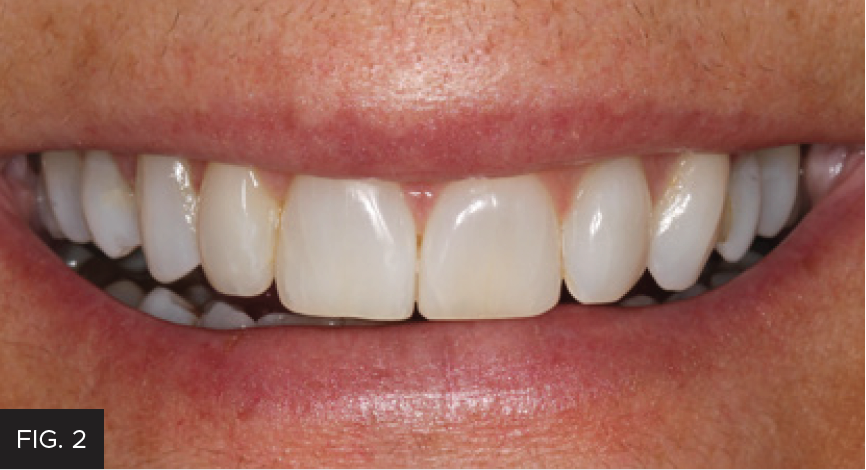

Examination and images, including the prescribed series of AACD photographs,2 revealed that #7 was normal, but smaller in crown size than ideal. Some tissue inflammation, likely related to orthodontic attachments, was visible on the tooth’s distal surface.The photographs and clinical data were reviewed with the patient. The main esthetic challenge would be to recreate incisal translucency and characteristics. (FIG 1 & 2)

Post-operative full smile view after orthodontic treatment completed and shows the completed composite restoration.